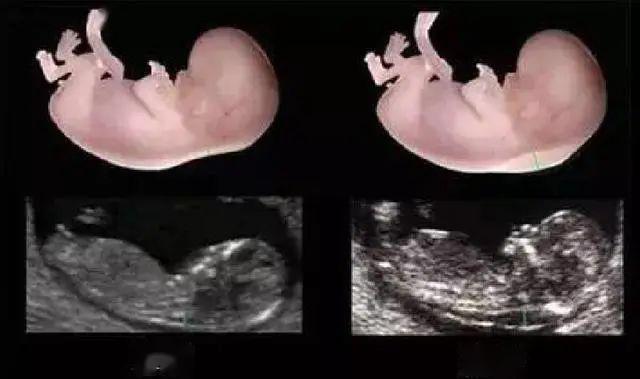

孕11周+1天~13周+6天

俗称的NT检查, 作用是对胎儿NT(颈项透明层厚度)的监测,以此评估胎儿结构与染色体异常的风险。

怀孕20~24周

孕中期系统筛查。即通常说的四维检查,这个时期是排查胎儿畸形的最佳时期,可以排查六大严重致死性畸形,对胎儿面部、神经系统、消化系统、泌尿系统以及其它系统的常见结构畸形做出筛查判断。这次检查也是5个阶段中最重要的一次超声检查,十分必要,耗时较长。